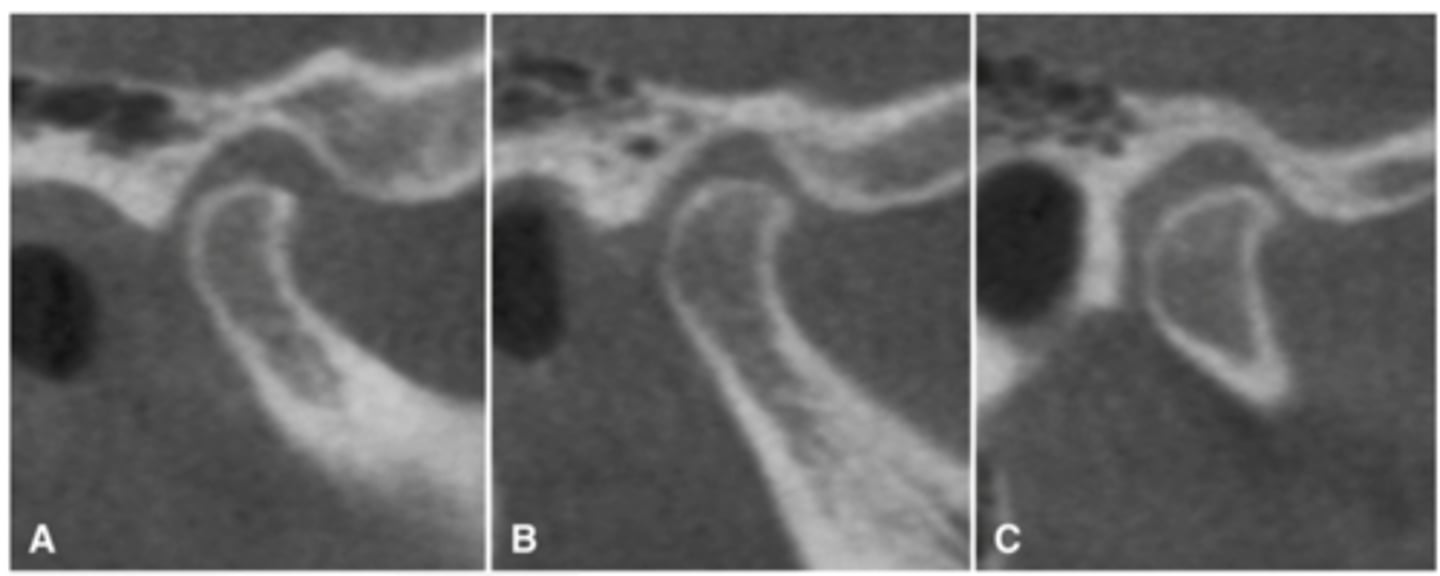

Patient has DJD, there is significant erosion and loss of joint space.

A and B show prominent osteophyte formation at the anterior aspect

C shows multiple subchondral erosions

What is the diagnosis of the patient based off these radiographs and what are the features?